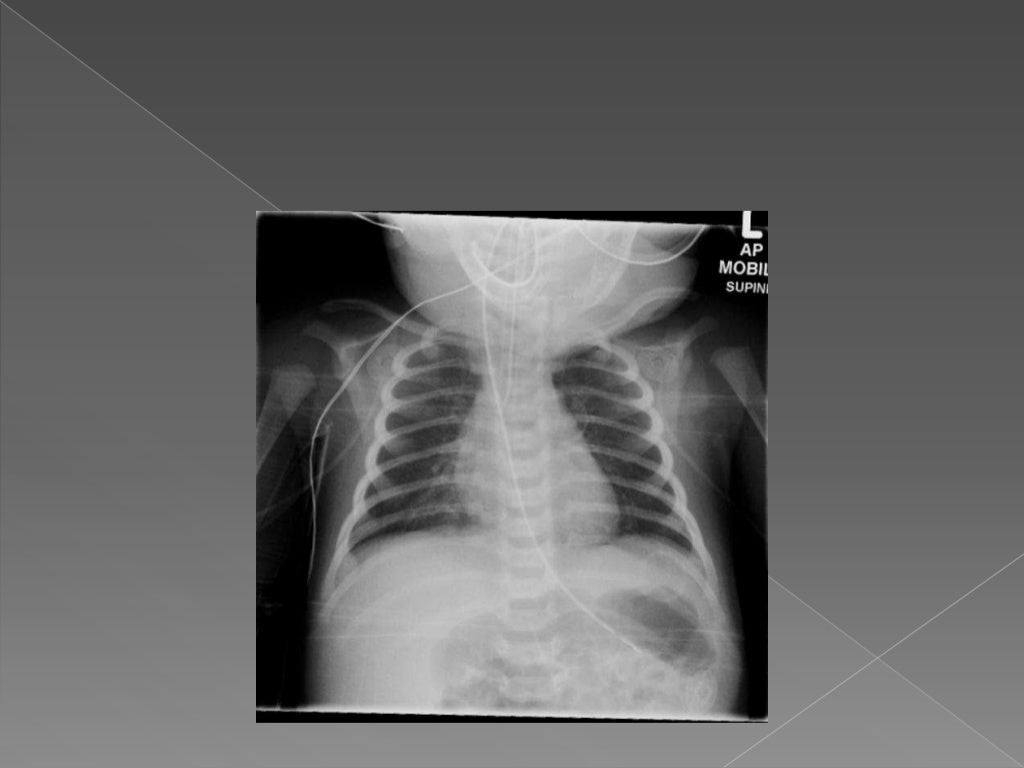

How To Read Neonatal Chest X Ray . basics of interpreting a neonatal chest radiograph. For evaluating the initial cause of respiratory distress. Neonatal unit, department of pediatrics,. the degree of rotation is best assessed by comparing the length of the anterior ribs visible on both sides. a specific finding on neonatal chest films is air leak tracking along the bronchi termed pulmonary interstitial emphysema (pie). (a) frontal chest radiograph at 3 months of age shows coarse interstitial opacities and overall mild hyperinflation. Standard chest radiograph is an anteroposterior. The specific reason why these radiographs are.

How To Read Neonatal Chest X Ray Standard chest radiograph is an anteroposterior. Neonatal unit, department of pediatrics,. For evaluating the initial cause of respiratory distress. basics of interpreting a neonatal chest radiograph. a specific finding on neonatal chest films is air leak tracking along the bronchi termed pulmonary interstitial emphysema (pie). the degree of rotation is best assessed by comparing the length of the anterior ribs visible on both sides. The specific reason why these radiographs are. Standard chest radiograph is an anteroposterior. (a) frontal chest radiograph at 3 months of age shows coarse interstitial opacities and overall mild hyperinflation.

Interpretation of Neonatal Chest Radiography How To Read Neonatal Chest X Ray Neonatal unit, department of pediatrics,. Standard chest radiograph is an anteroposterior. The specific reason why these radiographs are. the degree of rotation is best assessed by comparing the length of the anterior ribs visible on both sides. basics of interpreting a neonatal chest radiograph. (a) frontal chest radiograph at 3 months of age shows coarse interstitial opacities. How To Read Neonatal Chest X Ray.